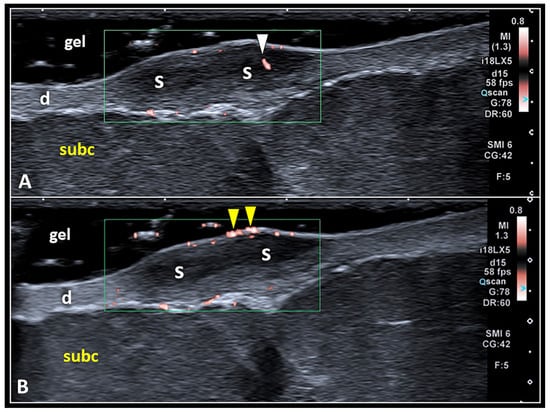

The edges of the scar can be ill-defined and poorly recognizable with a progressive passage from the scar to the normal dermis (coarse transition). They can also be well defined with a clear interface between the scar’s boundaries and the normal dermal tissue. The color/power Doppler assessment of scarring tissue requires accurate adjustment of technical parameters such as the Doppler gain/box and pulse repetition frequency [5,35]. The area of interest should be large enough to cover the entire scar; however, we suggest avoiding excessive sizes, which might decrease Doppler sensitivity in detecting low flows pertaining to small-size vascular elements (Figure 6) [36,37].

Figure 6.

Pitfalls in Doppler imaging of SS. Using a large amount of gel (i.e., the suspension technique) and fully including the scarring tissue (S) inside the Doppler box, it is paramount to accurately differentiate the real vascular signals (white arrowhead) inside the scar (A) from the ‘fake’ ones (yellow arrowheads) generated by the acoustic interface between the epidermis and the gel (B). d: dermis, subc: subcutaneous tissue.

Using color Doppler US and comparing with clinical scoring, Lobos et al., in 2017, published a retrospective study describing the vascular patterns of 42 clinically diagnosed Ks [11]. They proposed a color Doppler US grading of Ks (inactive in the absence of vascular signals, low and high in the presence of vessels) and concluded that clinical evaluation alone can underestimate the activity in Ks [11]. Also, using high-end machines (Canon Aplio i800, Canon Medical Systems, Shimoishigami, Otawara-Shi, Japan) and high-frequency US transducers (i18LX5, i33LX9), we can identify rare and small-size vascular signals inside the scarring tissue. We speculate that this finding may be related to the poor presence of vascular elements within a skin scar in the inactive phase (absence of inflammatory and remodeling phenomena). Of note, in clinical practice, the sonographic appearance of well-defined hyperechoic scarring tissue without inner neo-vessels usually defines a “mature” skin scar that has completed the active remodeling process. In such cases, if clinically indicated, manual treatments such as stretching and massages and physical agents such as superficial heat can be applied to the fibrotic tissue to improve the skin elasticity and the gliding of superficial soft tissues.

Likewise, artifactual flow signals at the gel–epidermis interface should not be misinterpreted as real vascular signals of the scarring tissue [27]. Indeed, fake vascular signals generated at the acoustic interface between the two different histological compartments are quite frequent during the musculoskeletal US and can be considered as a pitfall, especially for beginners. In this sense, minor shifts of the transducer over the target area or tiny changes in the pressure applied over the gel pad are very often tricks sufficient to promote the disappearance of these artifacts.